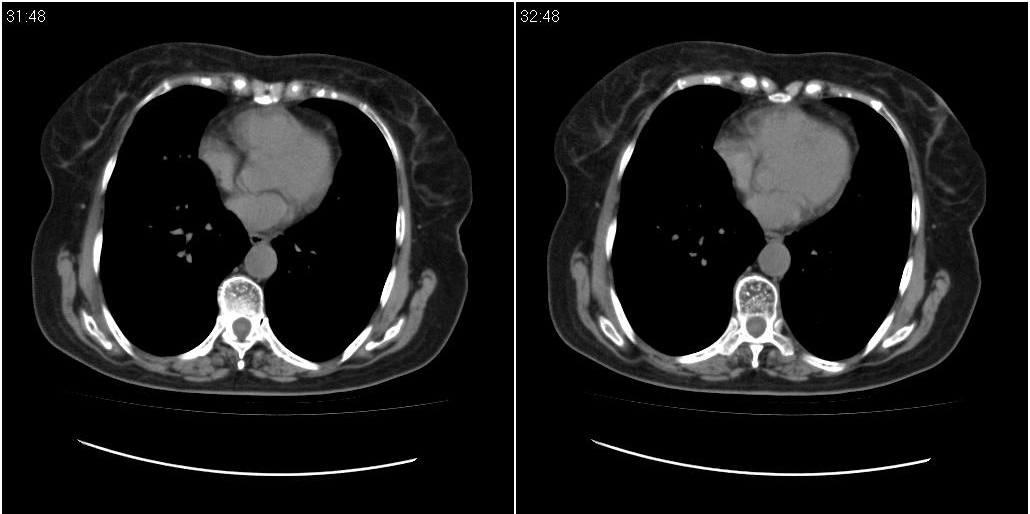

女性,72岁。去年9月份发现肺部病变,诊为肺结核并进行正规治疗至今,但复查后发现ct表现几乎没有变化。

双肺继发性肺结核并右肺中叶节段性肺不张,左下胸膜肥厚粘连。

双肺继发性肺结核并右肺中叶节段性肺不张

双肺继发型tb并右中叶内膜tb,轻度支扩,左下胸膜肥厚粘连。